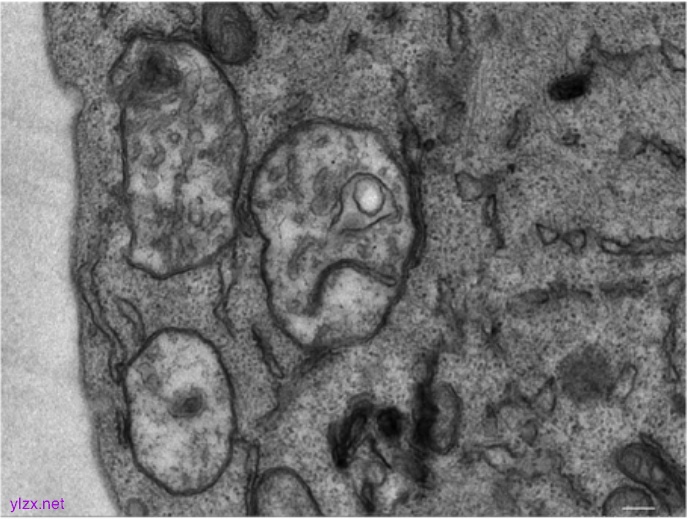

图3:透射电子显微镜显示顺铂作用下胆管癌细胞内质网自噬的发生

来源:原文图4